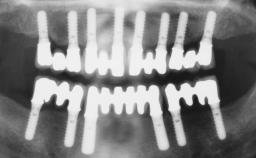

A fully edentulous 65-year-old woman was referred to our clinic for esthetic and functional dental rehabilitation. The patient presented with inadequate complete maxillary and mandibular prostheses, insufficient vertical dimension, and extensive tooth wear. The clinical examination and anamnesis showed no local or systemic contraindications, no signs or symptoms of bruxism, and an absence of smoking habits. The treatment proposed was implant placement in the mandibular interforaminal area and immediate loading with a fixed definitive prosthesis. A removable mucosa-supported complete prosthesis was indicated for the upper jaw, since its bone structure offered satisfactory retention and the financial condition of the patient disfavored a full-mouth implant-supported rehabilitation.

# of Implants 4

Type of Implants One-Piece

Loading Protocol Immediate

Retention Screw-retained, with 4 or more splinted implants Screw-retained, with 4 or more splinted implants